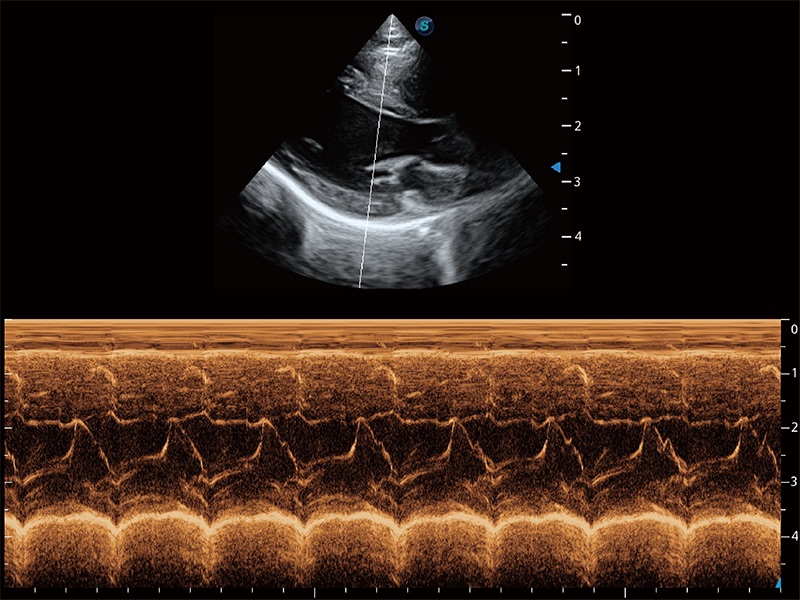

ProPet 80 配備了豐富的心臟探頭群、先進(jìn)的成像技術(shù)和專業(yè)的心臟測(cè)量工具,可幫助動(dòng)物醫(yī)生為不同體型和生理結(jié)構(gòu)的動(dòng)物提供心臟和心肌功能的全面評(píng)估。

實(shí)時(shí)用顏色表示心肌組織運(yùn)動(dòng),觀察和定量組織的運(yùn)動(dòng)情況,對(duì)快速檢測(cè)與評(píng)估心肌的灌注和活性、電傳導(dǎo)及心肌收縮和舒張功能等均能提供重要的診斷信息。